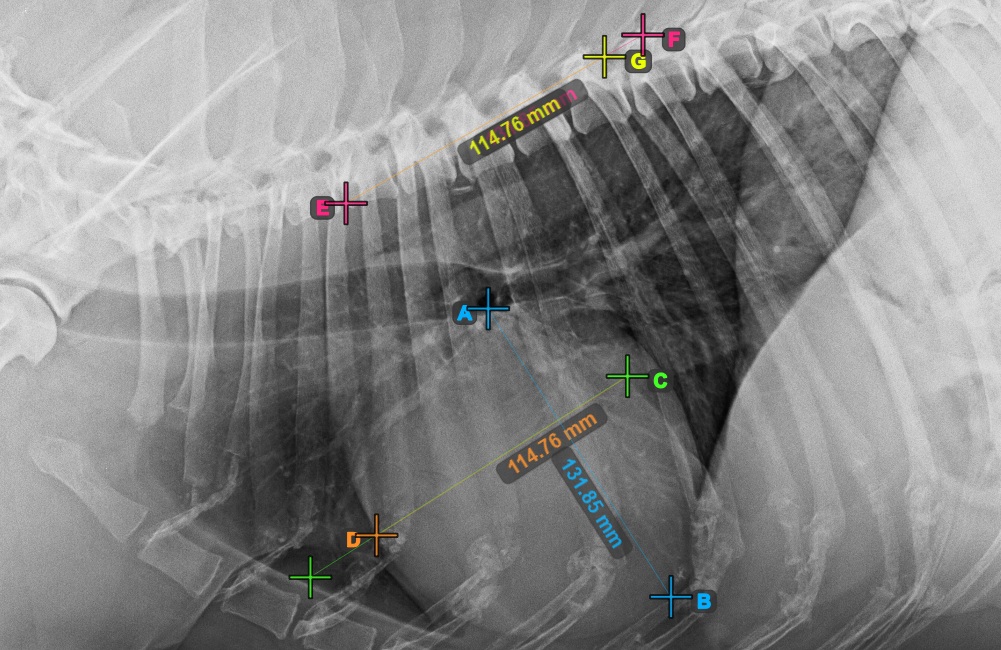

Starten Sie die Messung, indem Sie die Bifurcatio tracheae in der Nähe der Herzspitze markieren.

Das Bild unten zeigt die typische Platzierung des Punkts Bifurcatio tracheae.

Vervollständigen Sie die Längsachse des Herzens, indem Sie den Apex-Punkt in der Nähe der Herzunterseite markieren.

Das Bild unten zeigt die typische Platzierung des Apex-Punkts.

Fahren Sie mit der Messung fort, indem Sie den breitesten rechten (vorderen) Punkt der Kurzachse des Herzens markieren.

Das Bild unten zeigt die typische Platzierung des vordersten Punkts auf der Kurzachse des Herzens.

Vervollständigen Sie die Kurzachse des Herzens, indem Sie den breitesten linken (hinteren) Punkt markieren.

Das Bild unten zeigt die typische Platzierung des hintersten Punkts auf der Kurzachse des Herzens.